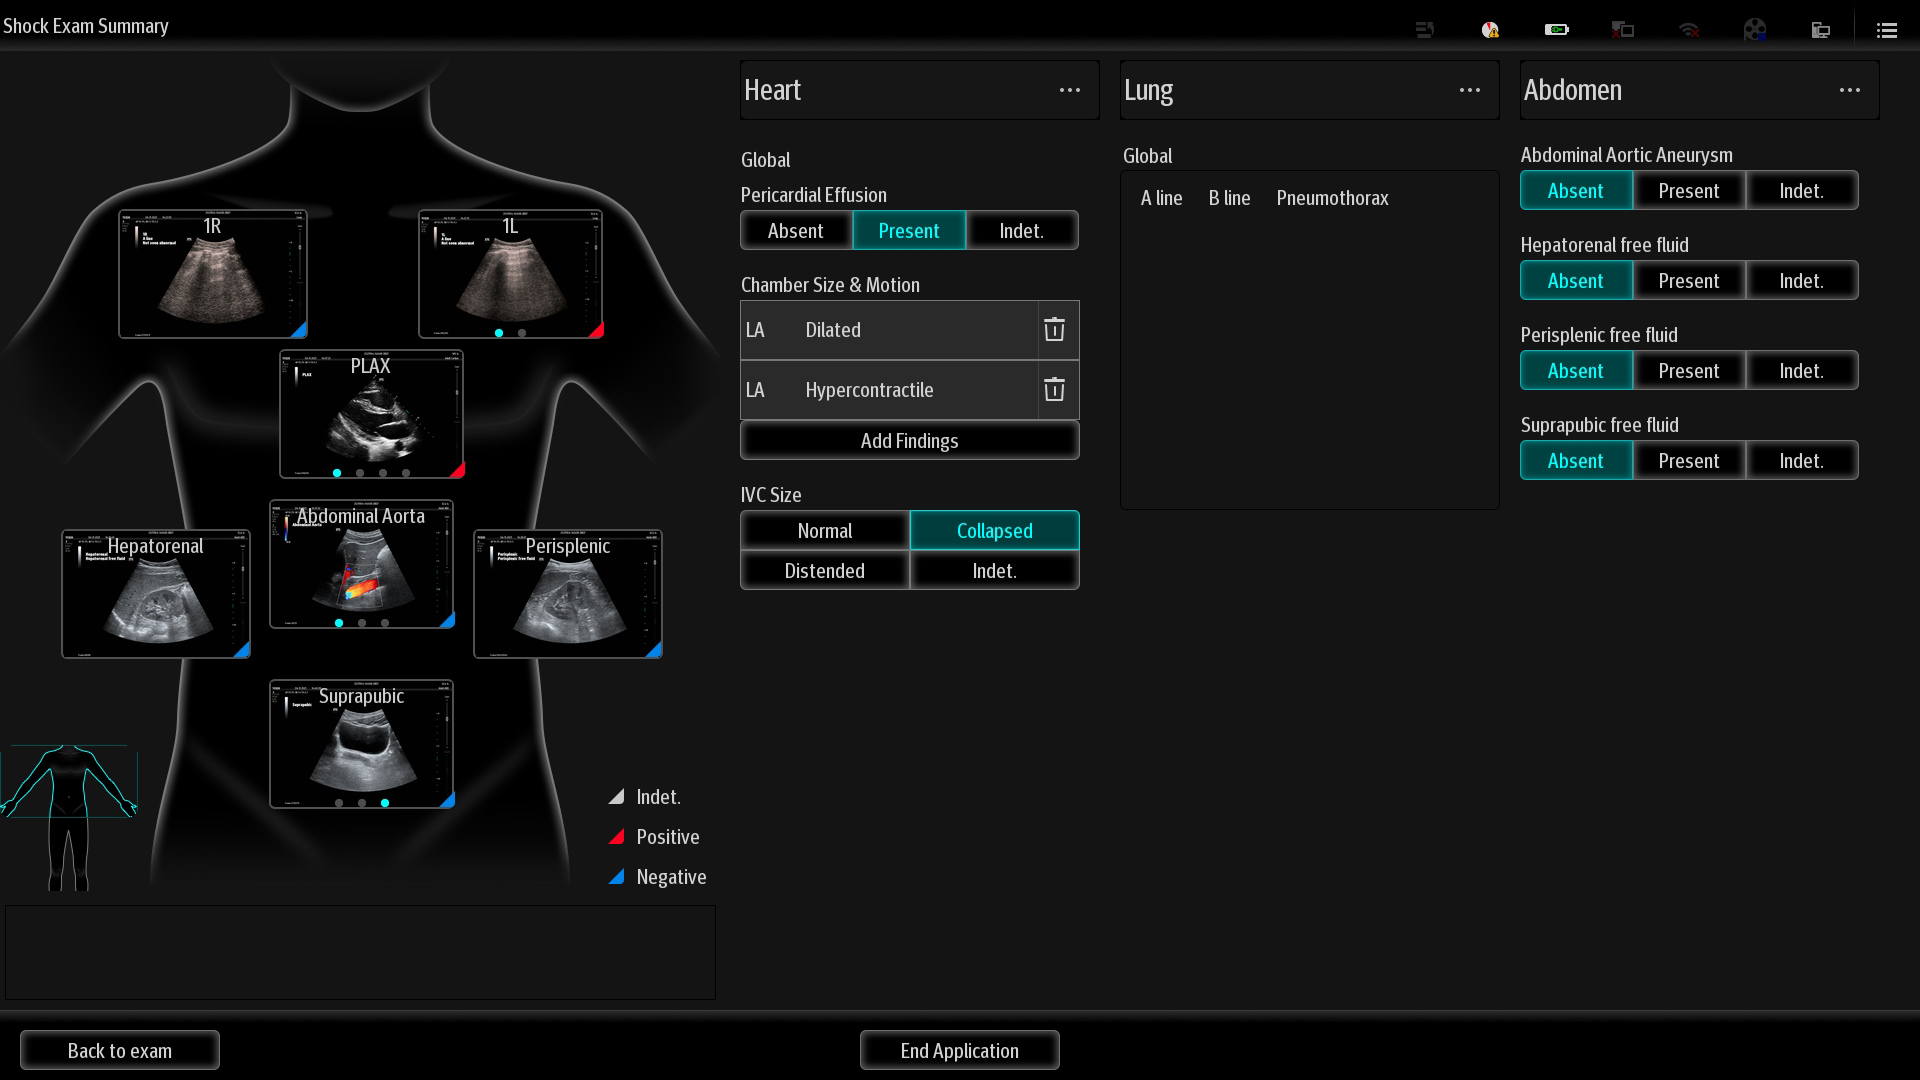

Critical Care

Ultrasound

Solutions

Reimagined quality clinical care

MindrayŌĆśs critical Ultrasound solutions drive improvements in care quality. Integrating advanced hemodynamic Ultrasound features, we can guarantee the highest standard of clinical care. The unique interoperability of Ultrasound and Vital sign data, we can provide comprehensive patient status data, to help inform clinical decisions, enhance clinical efficiency and, ultimately, improve patient outcomes.